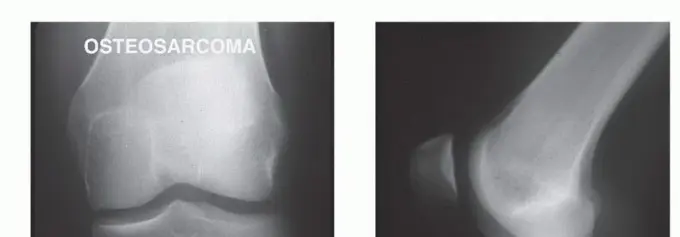

صورة شعاعية تظهر ساركوما عظمية في قصبة الساق القريبة لمريضة تبلغ من العمر 17 عاماً.

صورة شعاعية توضح ورماً عظمياً في قصبة الساق القريبة.

صورة شعاعية جانبية توضح ساركوما عظمية في قصبة الساق القريبة.

صورة شعاعية تظهر تدميراً قشرياً وامتداداً للأنسجة الرخوة للورم.